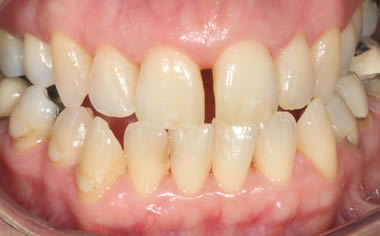

Gum disease

Case Three (2 images)

Treatment of moderate gum disease.